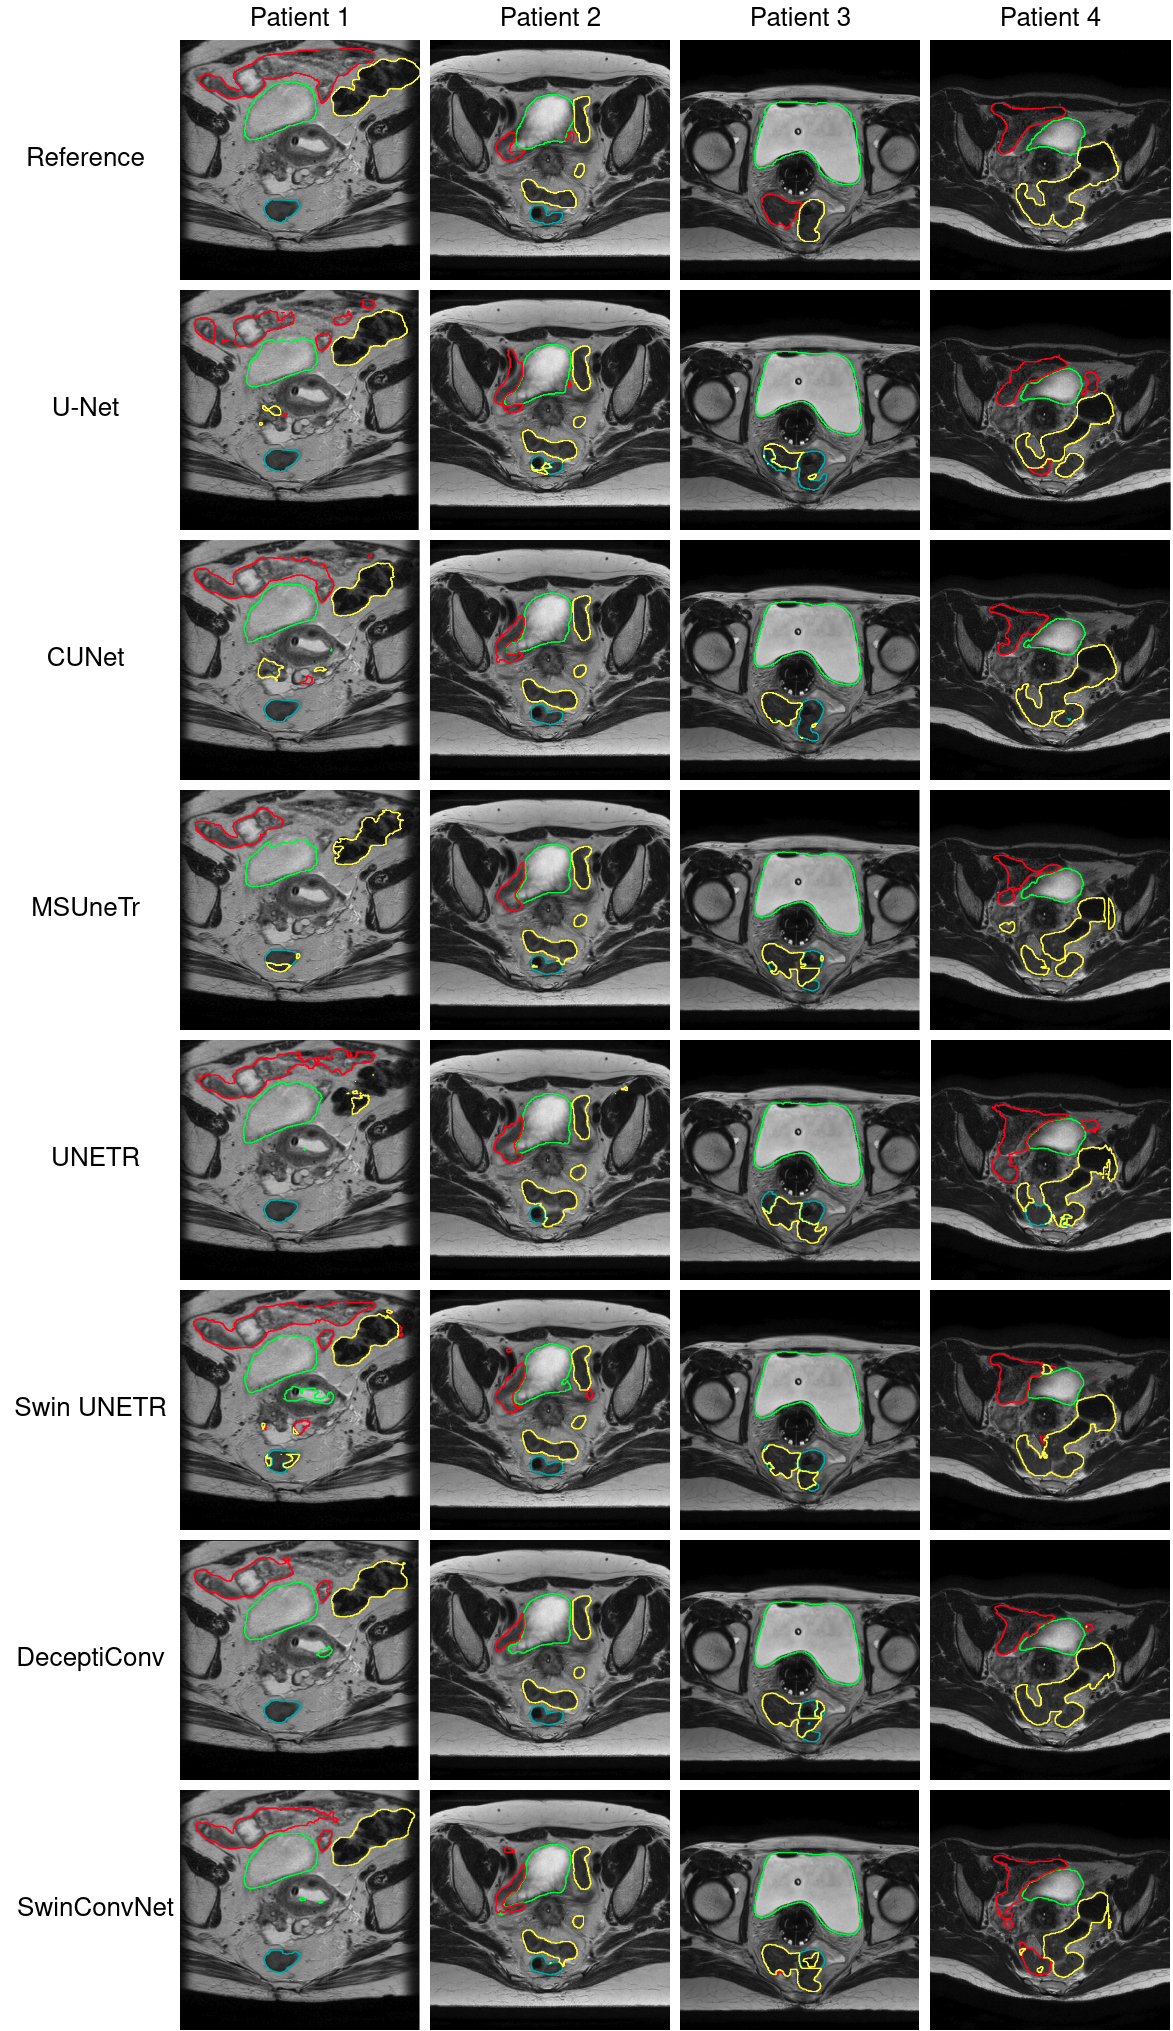

For visualization purposes, we calculate the average Dice Coefficient of every model, for every round in their 5-fold experiment, resulting in 5 scores per model. Then we average all these values for every fold, resulting in 5 final values. We sort them, and keep the fold that corresponds to the median of these values, which in our case was the 2ndsuperscript2𝑛𝑑2^{nd} fold. We randomly selected 4 patients from the validation set of this fold, from which we then selected 1 slice from each patient based on the reference that contains a lot of information. The results are presented in Figure 7 and Figure 8.

Refer to caption

Figure 7: Predictions of models on the Cervical Cancer Dataset. Green: bladder, Red: bowel, Cyan: rectum, Yellow: sigmoid.

The visual results of the predictions of the models, and the Dice scores between their predictions (most of them achieving >0.82absent0.82>0.82 Dice score) also indicate a high similarity in performance, but at the same time every model makes different mistakes. We can observe a high confusion of the models when predicting the sigmoid, bowel, and rectum, for the reasons we mentioned earlier. In order to mitigate this problem, it might be wise to follow a different approach than trying to segment the OARs separately (e.g., segment these three organs as one organ and then separate them). Nonetheless, to eventually decide which model is better in practice and whether its results are clinically acceptable, we have to conduct validation studies with doctors, something we are planning to do in the near future.